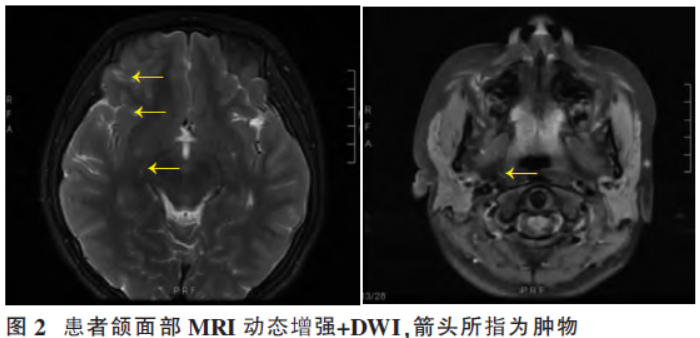

从R-CHOP到CAR-T,双病理淋巴瘤患者的三线治疗与合并症处置

病史摘要:59岁女性患者,2019年4月无诱因出现左眼睑肿胀,外院CT诊断“左眼眶内肿物”,症状逐渐加重。既往有乙型病毒性肝炎、子宫内膜癌子宫全切术病史。无发热、盗汗及体重下降。 诊疗过程:辅助检查包括颅脑增强MRI、CT、骨髓穿刺术等,诊断为非霍奇金淋巴瘤。一线行R-CHOP方案治疗6周期,后维持治疗;病情进展后二线行GEMOX方案化疗8周期及维持治疗;再次进展后三线入组临床研究,行自体